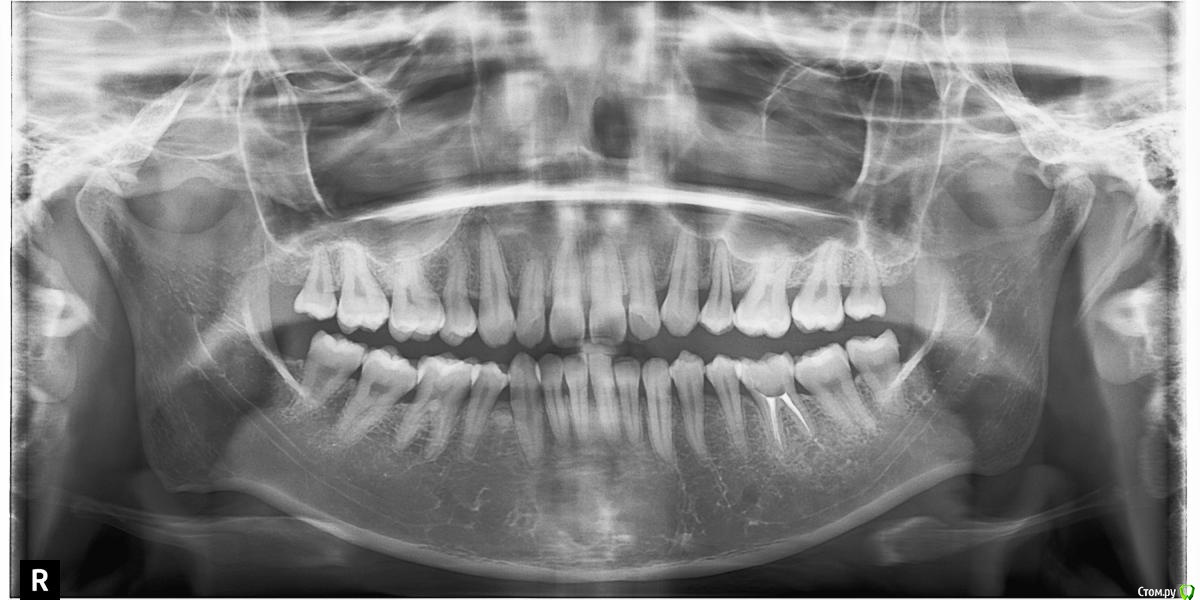

Головные боли, артроз ВНЧС, дистальный глубокий прикус, удалены 4ки на вч и 5 на нч

Сейчас мне 25 лет. С детства был дистальный глубокий прикус, зубы на верхней челюсти выпирали вперед, на нижней челюсти присутствовала скученность, из-за чего была удалена "мешающая" 5ка. Вероятно, этот зуб стоило сохранить.

В 2007-2008 гг. проходила ортодонтическое лечение с удалением 4ок на верхней челюсти. Резцовые зубы были перемещены назад, эстетически результат был удовлетворительным. Однако, проблема неправильного прикуса решена не была.

То, что эти боли могут быть следствием проблем с ВНЧС, узнала в последнюю очередь. МРТ показало, что у меня артроз суставов - 3 степени слева, полная вентрально-латерация дислокация суставного диска без репозиции; 1 степени справа, с репозицией, гипермобильность правого сустава. Асимметрии лица нет, однако рот открывается по S-образной траектории (почти не заметно), при широком открывании рта очень редко слышен щелчок, хрустов нет, слегка выпирает правый сустав. Заключение по МРТ с подробным описанием в приложении.

Заключение по МРТ, ОПТГ, цефалограмма в боковой проекции (справа и слева) и фото зубов - в приложении.

Все снимки по результатам КЛКТ (5 мб) можно скачать по ссылке https://www.dropbox.com/s/4c026r3ewd8zz0l/KLKT.zip?dl=0